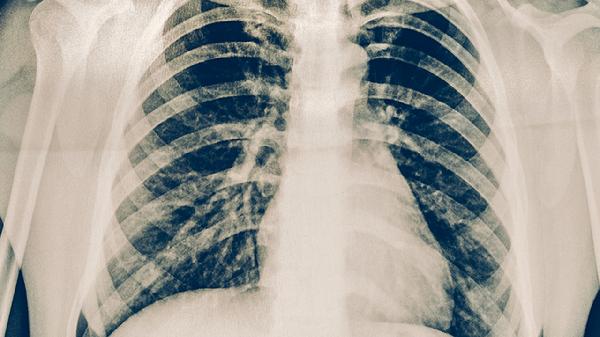

治疗期间保持清淡饮食,避免海鲜、芒果等易致敏食物,每日饮水2000毫升促进药物代谢。选择宽松纯棉衣物减少摩擦,室内湿度维持在50%-60%防止皮肤刺激。严格遵医嘱完成结核全程治疗,定期复查胸片与痰菌检测,出现新发瘙痒需立即与主治医生沟通调整方案。保持规律作息有助于提升药物耐受性,避免日光直射加重光敏反应。